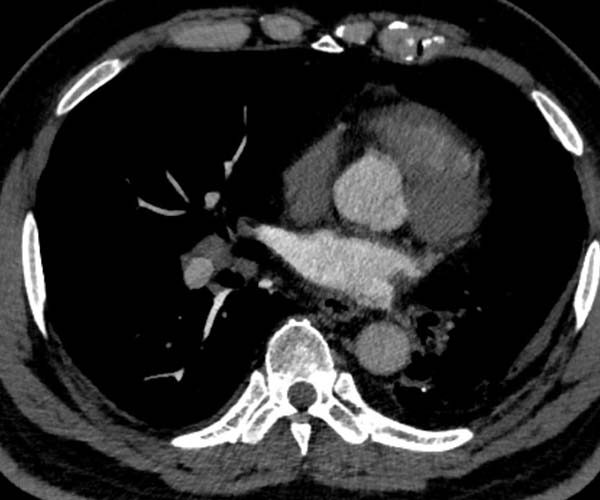

在应用间接法-智能追踪扫描方式时,如果留置针位置选择不当,可能会出现大部分对比剂未能第一时间参与灌注,导致在肺循环中对比剂与血液比例远低于正常值,即便达到靶血管的阈值,而感兴趣区CT值仍然过低,影响诊断。

灌注不足 主动脉弓CT值过低